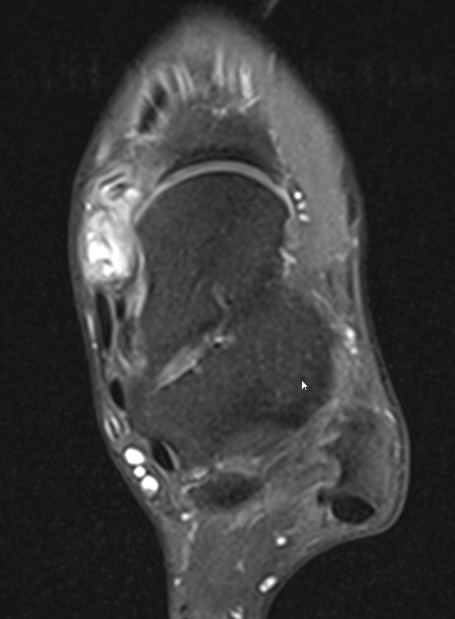

GCT flexor tendon sheath

GCT of tibialis posterior tendon sheath